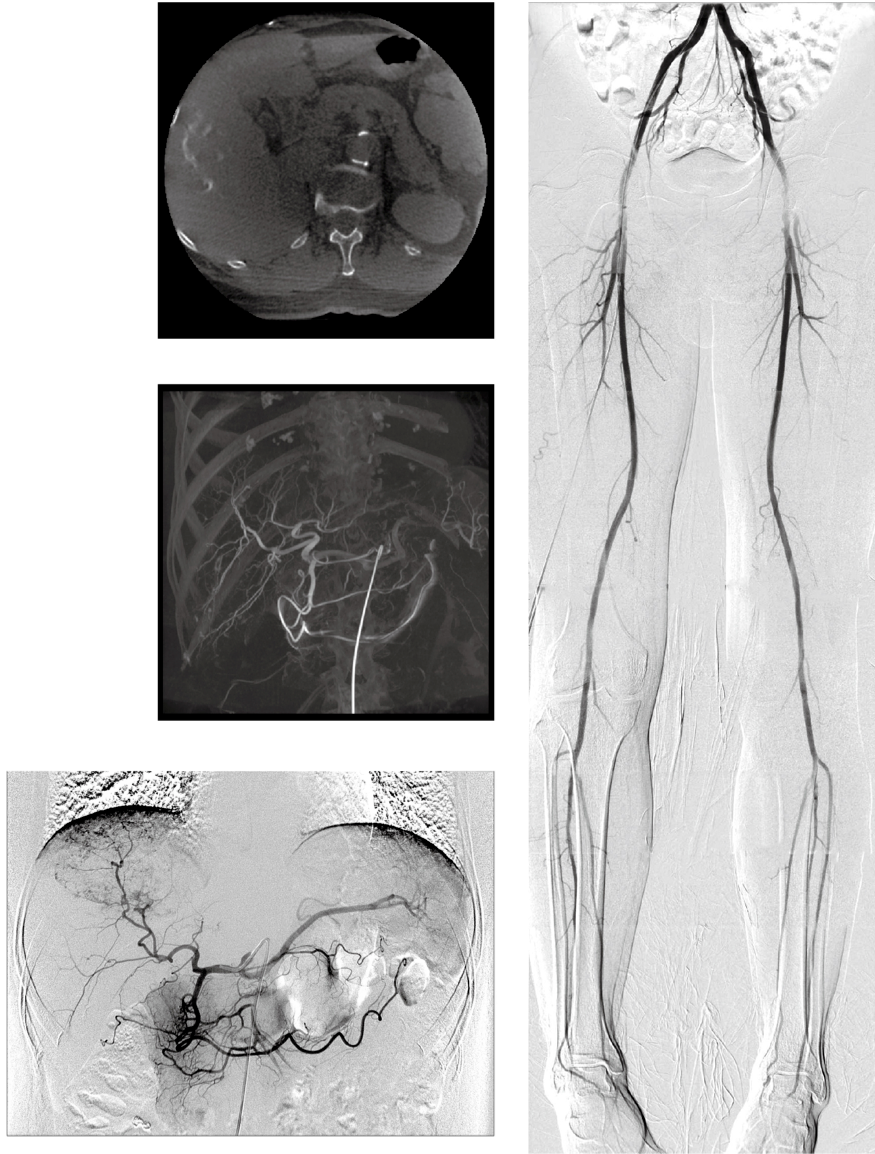

Designed to examine from the tip of the foot to the head… without moving the patient

Combine live images with 2D and 3D projections along with tomographic slices on site

Clinical Images